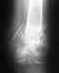

На лекарства здесь вряд ли стоит полагаться. Наиболее надежно, если нет прроявлений инфекции, закрыто ввести стержень в костномозговой канал? и запереьб его винтами. Переломов больше не будет, ходить можно сразу. Пример см. здесь